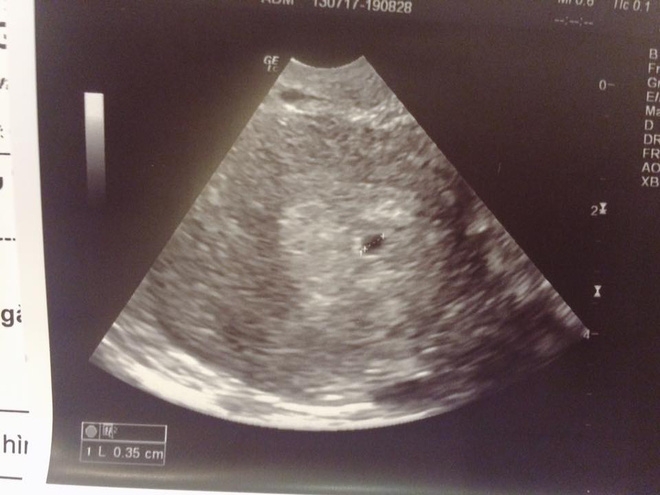

"Con của em được 5 tuần rồi. Em có nói chuyện với mẹ (vì bọn em có bé trước khi cưới) mà mẹ em thì rất tin vào bói toán. Mặc dù biết người yêu hơn em 11 tuổi (sinh năm 83) nhưng nhất định mẹ bắt em phải sau 27 mới được lấy và 28 mới được có em bé, vì bà ngoại em đi xem bói ở đâu đó nói nếu em lấy chồng trước 27 tuổi thì đến năm 32 tuổi vợ chồng em sẽ ly hôn.

Sau khi em báo tin có bầu, mẹ em hỏi han về anh người yêu, rồi hỏi sẽ sống như thế nào. Em nói lương anh ấy ổn định (vì là người nước ngoài làm ở Việt Nam nên lương tháng cũng 60 triệu chưa kể tiền trợ cấp ăn) mẹ không cần lo lắng quá. Vậy mà mẹ em vẫn nói "60 triệu thì là cái gì". Em vẫn cảm thấy sợ mẹ em sau câu nói "mới có 5 tuần bỏ cũng được chứ sao"... Em hận bản thân vì không thể làm gì hơn...

| "Em thấy sợ chính mẹ đẻ khi bà thản nhiên nói bỏ cháu ruột mình mới 5 tuần tuổi" (Ảnh minh họa). |